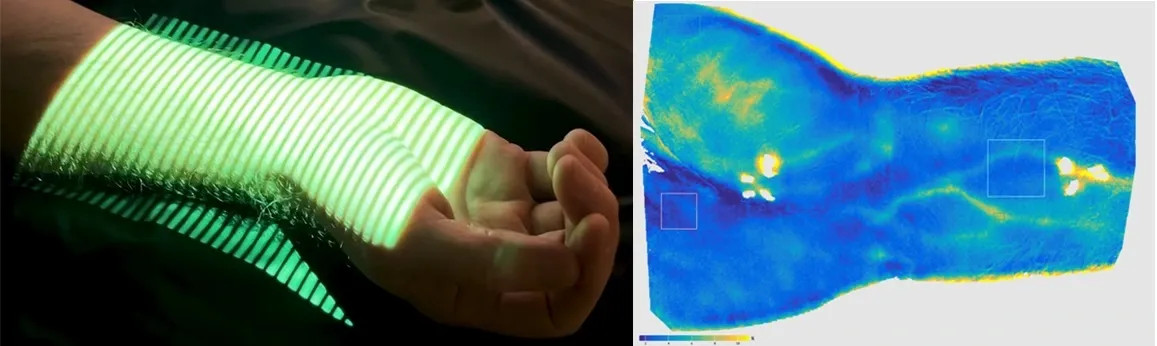

Forskare vid Karolinska Institutet har i en ny studie från 2026 undersökt hur mikrocirkulationen påverkas vid allvarlig sjukdom och hur detta i sin tur påverkar kroppens förmåga att fungera och återhämta sig.

Tänk om vi kunde upptäcka hjärt-kärlsjukdom innan den ens visar sig? Det är precis vad svenska SCAPIS-studien (Swedish CArdioPulmonary bioImage Study) nu banar väg för. Med över 30 000 deltagare och världsledande bilddiagnostik kartlägger forskare riskfaktorer för hjärt-, kärl- och lungsjukdomar, och en delstudie sticker ut i sammanhanget: SCAPIS...